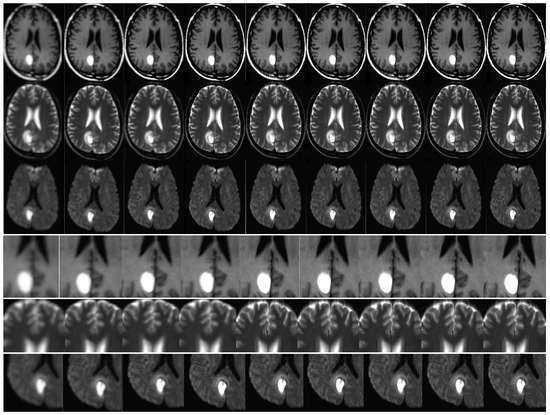

The effectiveness of the algorithm was assessed through the analysis of in vivo patient cases and phantom data. The MATLAB software was utilized for conducting all trials and investigations. The objective of the assessments was to assess the effectiveness of super-resolution image reconstruction through the utilization of compressed input. An additional aim was to assess the efficacy of the MR sampling technique. This study involved the analysis of both in vivo and phantom data. The simulation results are illustrated in Figure 8 and Figure 9. It is noteworthy that the utilization of Compressed Sensing in conjunction with its conjugate symmetry and partial Fourier technique expedites the process of data acquisition in comparison to alternative unaltered k-space sampling patterns. The analysis of human data involved the processing of Siemens Prisma scanner files, which had a measurement of 3.0 terabytes. In order to replicate the performance of a multi-channel head coil across a range of in-plane resolutions, diffusion directions, and slice thicknesses, fully sampled k-q spaces have undergone decimation. The denoising problem is defined within the framework of Maximum A Posteriori (MAP) estimation by the proposed method. The algorithm for noise reduction under consideration yields an average value of approximately 2.1 dB, as determined by the tests conducted. Phantom-based experiments were conducted on high-quality DW multi-shot EPI sequences. The simulation of off-resonance effects was conducted utilizing fugue. The study employed D-BRAIN phantom models, which are diffusion MRI brain data models that are anatomically precise. The training of the model was conducted on an NVIDIA DGX machine equipped with GPU A100, utilizing the resources of Google Colab Pro. The generator undergoes training using a pair of LR images, which are stacked and have dimensions of 60 × 60 × 2. The objective is to generate a single HR image with dimensions of 240 × 240. The generator employs a tripartite loss function comprising of content loss, perceptual loss, and adversarial loss. The discriminator is subjected to both the SR and HR images obtained from MRI. The binary classifier known as the discriminator employs binary cross-entropy as its optimization technique. The utilized optimizer is Adam, which is applied to both the generator and discriminator. The learning rate is 10 5 (Table 1, Table 2, Table 3, Table 4 and Table 5).

The present study incorporates the technique of compressed-sensing with super-resolution image reconstruction for application in Magnetic Resonance Imaging scanners. The utilization of phantom data has been employed to expose the inverse challenges associated with compressed sensing in the context of magnetic resonance imaging (MRI). The utilization of sparse projections has been observed in the retrieval of Shepp–Logan phantom data, as depicted in Figure 8. Twenty-five and twelve radial lines in the frequency domain are capable of reconstruction. The data reconstruction process employed by the author involves utilizing a subset of sixty projections within a ninety-degree aperture to reconstruct data from limited-angle projections. The method employed for the creation of all Shepp–Logan phantom images was this. The input frame was degraded by a nonrigid transformation. The application of rotation and subpixel shift factors was carried out in the following manner. Local affine simulations were utilized to model motion artifacts of internal organ tissue in order to demonstrate blurring. The low-resolution photos were subjected to a Gaussian blur kernel resulting in blurring. Subsampling using a predetermined ratio will ensue. The addition of white Gaussian noise occurred subsequently. The noise level of the test photos was measured to be twenty-five standard deviations. The recording of deformable medical images presents a challenge. The utilization of Markov random field (MRF) optimization in a registration method based on structural representation reduces the dimensionality of transformation parameters and imposes constraints on energy function values in the image region associated with non-rigid deformation.

Please refer to Figure 7 and Figure 8 for empirical support of the enhancement in both image resolution and quality. The improved resolution and legibility of the procedures utilized for potentially malignant or premalignant lesions have resulted in an increased capacity to detect them. The method’s anticipated efficacy is largely attributed to its potential advantages, such as achieving a heightened contrast while preserving a superior level of resolution. The present study investigates the integration of magnetic resonance (MR) with super-resolution and compressed-sensing techniques. The enhancements that were obtained have led to notable improvements in sharpness, edge interpretation, and contrast. The achievements have been verified by PSNR as well. The impact of CS quality ratios on PSNR values is significant, as demonstrated by the Table 1, Table 2, Table 3, Table 4 and Table 5.

The average peak signal-to-noise ratio (PSNR) is computed by utilizing various method outputs and ground truth images. The simulation was conducted on one hundred occasions. To ensure the statistical reliability of quality measurements, the PSNR calculation procedure was replicated for every simulation case and subsequently averaged. It is noteworthy that the most favorable outcomes were achieved utilizing a compression ratio of 50%. This implies that a further reduction in the overall quantity of input samples leads to a slight improvement in the peak signal-to-noise ratio (PSNR), as evidenced by the data presented in Table 1, Table 2, Table 3, Table 4 and Table 5. The reduction in exam duration is directly proportional to this particular value. Furthermore, this approach has the potential to mitigate motion distortions in addition to compromising on resolution. The approach centers on expediting the convergence of algorithms, incorporating image prior, and recognizing blur kernels. Preliminary trial data can serve as valuable background information to expedite the duration of examinations. Notwithstanding the capability of the motion estimation algorithm to significantly mitigate diagnostic image artifacts, thereby enhancing the probability of an accurate diagnosis; it is incapable of completely eliminating all artifacts. Figure 8 and Figure 9 demonstrate an enhancement in the resolution and caliber of the outcomes acquired. The results mentioned above are provisional and susceptible to modification. The algorithm’s advantages were demonstrated through a qualitative evaluation of the neuroimages of twenty patients. The study involved the collection of DW-MRI data from twenty patients with oncological conditions, using a single scanner. The calculation of the mean square error (MSE) was performed for each instance of reconstruction in order to obtain statistically significant measurements. The study employed the signed rank test to examine the null hypothesis that the central tendency of the difference across different sparsity rates was equivalent to zero. The statistical analyses were conducted using the R Project for Statistical Computing. A statistical analysis was performed utilizing a t-test for independent groups to compare the mean values of peak signal-to-noise ratio (PSNR) between two distinct groups. Additionally, a paired t-test was conducted to analyze paired data. The algorithm’s robustness has been confirmed by the probability, which was determined through a significance test and Student’s t-test conducted on the PSNR. The outcomes are exhibited in Table 3, Table 4 and Table 5. The statistical significance of the results was high, as indicated by the obtained p-values.

The study conducted a comparison between the proposed algorithm’s robustness and other existing image resolution enhancement algorithms, namely, bicubic spline interpolation, Yang’s N-R-M-3D [57] (3DKR) as cited in reference [4], and IBP that utilizes optical flow-based motion estimation as its fundamental technique. The results of the comparison are presented inTable 1, Table 2, Table 3, Table 4 and Table 5. The results are visually represented through the use of graphical illustrations, as evidenced by Figure 8. The obtained outcomes have been contrasted with four advanced super-resolution image reconstruction techniques, namely, sightly modified the MRI super-resolution using GAN and DWT [43] and the brain MRI super-resolution using 3D GANs [44] Yang’s N-R-M-3D [57], Lim’s E-D-R-N-S-I-S-R [58], RCAN SRR [60], and Zhang’s R-D-N-I-S-R [59]. The Lim’s E-D-R-N-S-I-S-R [58], RCAN SRR [60], z z Zhang’s R-D-N-I-S-R [59] methods employ the L 1 -loss function for network training purposes.